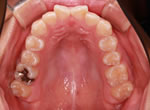

施術前

施術後